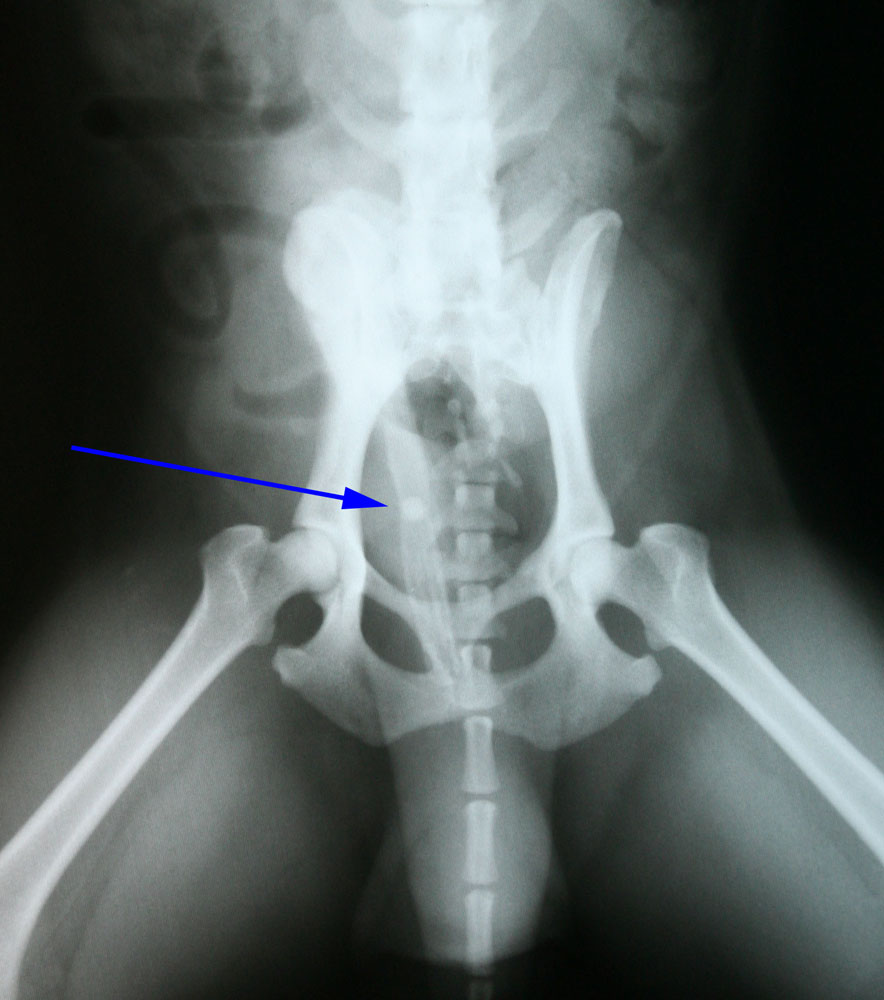

Hierna hebben we een urinekatheter ingebracht die na 4 cm vastliep op een harde structuur. Op de röntgenfoto is er bij de pijl een blaassteen te zien die vastgelopen is in het penisbotje.

Na verder onderzoek verricht te hebben kwamen we tot de conclusie dat er in de blaas zelf nog wat gruis zat en mogelijk zeer kleine steentjes.